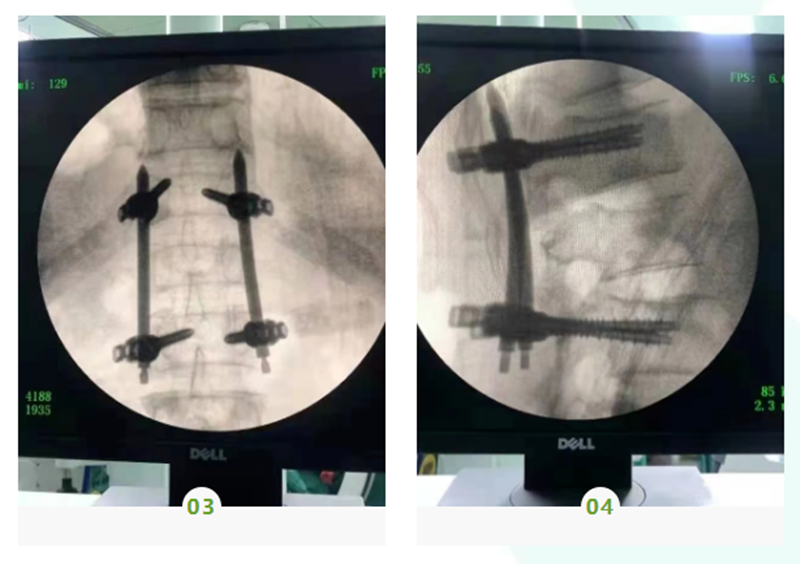

我科目前开展的骨科新技术项目包括:创伤骨科:交锁髓内钉内固定治疗四肢长骨干骨折、股骨近端髓内钉(PFNA、intertan)治疗股骨粗隆间骨折、经皮微创接骨板技术(MIPO)治疗胫腓骨骨折、弹性髓内钉闭合复位治疗儿童四肢骨折等,上述微创技术在四肢骨折中的运用均符合生物学原则,具有创伤小、术中出血少、术后恢复快等优点;关节外科:人工半髋及全髋关节置换术、人工全膝关节置换术、膝关节镜下半月板成形术及交叉韧带重建术等;脊柱外科:开展经皮椎间孔镜下治疗腰椎间盘突出症、经皮椎体后凸成形术微创治疗老年骨质疏松性椎体压缩性骨折、颈椎前路手术治疗混合型颈椎病等;显微外科手术:肌腱、血管吻合术、断肢(指、趾)再植术等。其中髓内钉及MIPO技术、人工全膝及全髋关节置换术、关节镜手术及手足显微外科手术均在我院率先开展,居于领先水平。